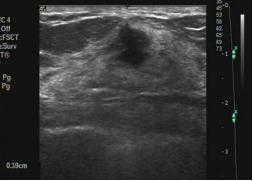

3.乳腺结节的边缘。

分为:光整和不光整(模糊、成角、微小分叶、毛刺等)。边缘光整是指:结节的边缘与周围组织界限清晰,往往是良性结节的特征。结节边缘不光整往往是乳腺癌的征象,指的是:模糊(结节的部分边缘无清晰的边界)、微小分叶(结节边缘出现锯齿状结构)、成角(结节边缘部分或全部形成锋利的角度,通常为锐角)、毛刺(从结节的边缘放射状的锐利细线)。

结节边缘为微小分叶,术后病理为恶性

结节的边缘成角,是恶性的表现